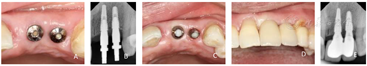

(5)终义齿修复:种植二期手术1个月后,取下21、22愈合基台,见牙龈袖口质地坚韧,高度约2 mm,局部清理消毒,旋入印模柱,X线片检查确认印模柱就位,制取开口式硅橡胶印模,比色,制作21、22钴铬合金烤瓷联冠,2周后完成终义齿修复(图6)。

因患者常年旅居外地,种植修复后定期进行电话回访,反馈功能及美观性良好。种植修复后2、6年来院复查,21、22种植修复体完整、稳固,咬合检查未见高点及牙合干扰,近、远中邻接关系良好,龈缘未见明显退缩,牙龈颜色、形态、质地正常,未探及牙周袋。X线片显示21、22种植体周围无透射影、垂直方向未见明显骨吸收。行全口牙周洁治,植体周维护,口腔卫生宣教(图7)。